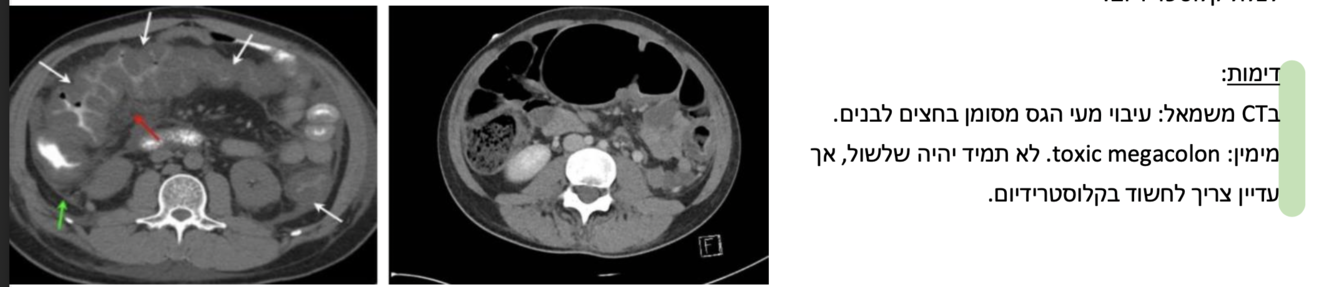

Toxic megacolon- יכול להיגרם מהיתקעות תוכן במעי.

כאשר יש לויקוציטוזיס משמעותי (20,000+) לא מוסבר נחשוד בקלוסטרידיום ונטפל בהתאם כדי למנוע סיבוכים .